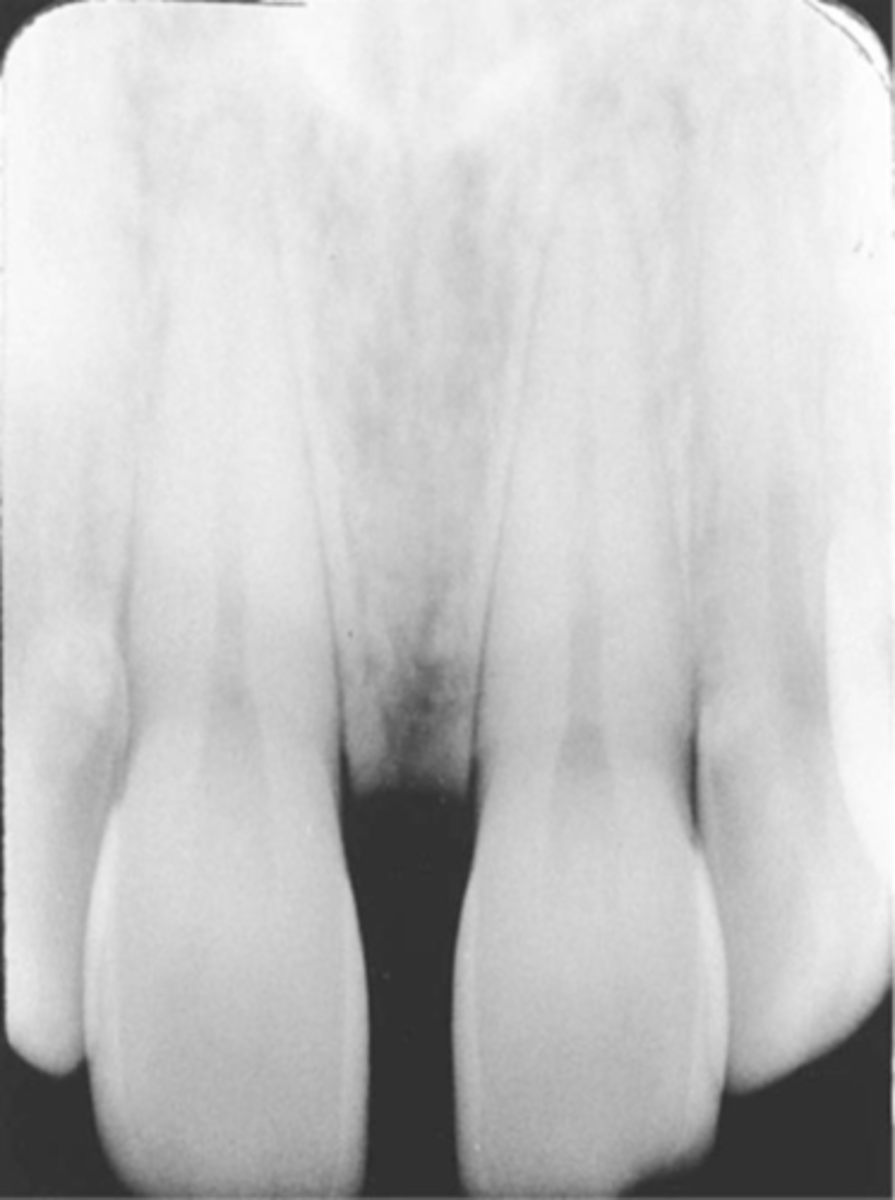

Incorrect Horizontal Angulation

-Overlapped contacts

-CR was not directed through the interproximal spaces, resulting in the proximal surfaces of adjacent teeth appear overlapped in the PA.

-Occurs in both paralleling and bisecting technique

-To prevent direct the x-ray beam through the interproximal regions

Incorrect Horizontal Angulation -->Bite-Wing

-CR was not directed through the interproximal spaces.